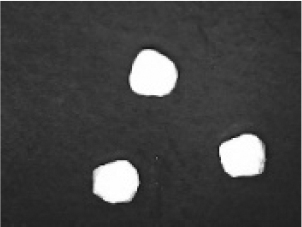

In addition to the disintegration endpoint studied using the USP disintegration apparatus, the pellets disintegrated into particles of various sizes when evaluated at a static position. A few drops of water were placed on the pellets on the opaque surface. A USB digital microscope (China) was connected to a computer to capture the disintegration process. Images were captured from the beginning until the pellet disintegrated or exploded into small fragments. Pellet images were acquired every 30 seconds. for formulations containing polyplasdone XL 10 and croscarmellose sodium.

Disintegration was evaluated at room temperature under static conditions. The camera captured images every 30 s ( Table 9), illustrating that MCC pellet X3 with mannitol and PEG 400 did not disintegrate. Within 120 s, cracks appeared in P5 pellets containing mannitol, PEG, and PPXL. As seen in the C4 pellets, they begin to explode into many fragments within 30 s. Moreover, the CP12 pellets containing PEG 400, mannitol, CCS, and PPXL began to explode into many loosely linked particles after 60 s, which quickly separated under the oscillating motion of the USP disintegration equipment. The photographs are compatible with the results mentioned above for the USP disintegration device. When the temperature was increased to 37°C, the disintegration caused the split into tiny fragments.

Table 9. Camera capture of pellet disintegration at different time intervals.

Pellet # 0 sec. 30 sec. 60 sec. 90 sec. 120 sec.

X3c9c3975f-9288-4951-a800-a8e9fc463382_GRA58.gif c9c3975f-9288-4951-a800-a8e9fc463382_GRA59.gif c9c3975f-9288-4951-a800-a8e9fc463382_GRA60.gif c9c3975f-9288-4951-a800-a8e9fc463382_GRA61.gif c9c3975f-9288-4951-a800-a8e9fc463382_GRA62.gif

P5c9c3975f-9288-4951-a800-a8e9fc463382_GRA63.gif c9c3975f-9288-4951-a800-a8e9fc463382_GRA64.gif c9c3975f-9288-4951-a800-a8e9fc463382_GRA65.gif c9c3975f-9288-4951-a800-a8e9fc463382_GRA66.gif c9c3975f-9288-4951-a800-a8e9fc463382_GRA67.gif

C4c9c3975f-9288-4951-a800-a8e9fc463382_GRA68.gif c9c3975f-9288-4951-a800-a8e9fc463382_GRA69.gif c9c3975f-9288-4951-a800-a8e9fc463382_GRA70.gif c9c3975f-9288-4951-a800-a8e9fc463382_GRA71.gif c9c3975f-9288-4951-a800-a8e9fc463382_GRA72.gif

CP12c9c3975f-9288-4951-a800-a8e9fc463382_GRA73.gif c9c3975f-9288-4951-a800-a8e9fc463382_GRA74.gif c9c3975f-9288-4951-a800-a8e9fc463382_GRA75.gif c9c3975f-9288-4951-a800-a8e9fc463382_GRA76.gif c9c3975f-9288-4951-a800-a8e9fc463382_GRA77.gif

CPP4c9c3975f-9288-4951-a800-a8e9fc463382_GRA78.gif c9c3975f-9288-4951-a800-a8e9fc463382_GRA79.gif c9c3975f-9288-4951-a800-a8e9fc463382_GRA80.gif c9c3975f-9288-4951-a800-a8e9fc463382_GRA81.gif c9c3975f-9288-4951-a800-a8e9fc463382_GRA82.gif

CPO4c9c3975f-9288-4951-a800-a8e9fc463382_GRA83.gif c9c3975f-9288-4951-a800-a8e9fc463382_GRA84.gif c9c3975f-9288-4951-a800-a8e9fc463382_GRA85.gif c9c3975f-9288-4951-a800-a8e9fc463382_GRA86.gif c9c3975f-9288-4951-a800-a8e9fc463382_GRA87.gif

The CP12 pellet disintegration process is depicted in the video in the supplementary material (refer to underlying data). The pellets swelled immediately before exploding and quickly disintegrating. The orphenadrine citrate pellets began to swell and cracks appeared after 120 s, which were easily separated under the oscillating motion of the USP disintegration equipment. The photographs are compatible with the results of the USP disintegration device. When the temperature was increased to 37°C, disintegration caused the fragments to split into smaller fragments. When the temperature was increased to 37°C, disintegration caused the split into tiny fragments. The pseudoephedrine hydrochloride pellets began to explode into several pieces of loosely linked particles within 120 s, which were easily separated by the oscillating motion of the USP disintegration equipment. The photographs were compatible with the results obtained from the USP disintegration device. When the temperature increased to 37°C, the disintegration caused the split into tiny fragments. Although this is not an official USP test, using video capture for disintegration validates Chamsai’s claim of quick disintegration.18